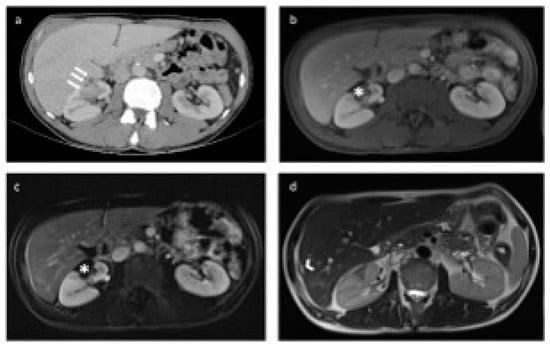

2.1. Percutaneous Microwave Ablation Therapy

2.3. Laparoscopic Ultrasound-Guided Percutaneous Microwave Ablation Therapy